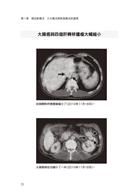

短短半年就讓我的三個轉移肝癌腫瘤消失了__坂本佳子女士(假名‧61歲)